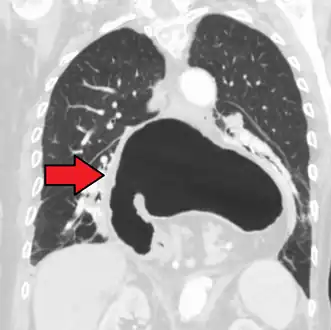

The diagnosis of a hiatal hernia is typically made through an upper GI series, endoscopy, high resolution manometry, esophageal pH monitoring, and computed tomography (CT). Barium swallow as in upper GI series allows the size, location, stricture, stenosis of oesophagus to be seen. It can also evaluate the oesophageal movements. Endoscopy can analyse the esophageal internal surface for erosions, ulcers, and tumours. Meanwhile, manometry can determine the integrity of esophageal movements, and the presence of esophageal achalasia. pH testings allows the quantitative analysis of acid reflux episodes. CT scan is useful in diagnosing complications of hiatal hernia such as gastric volvulus, perforation, pneumoperitoneum, and pneumomediastinum.[8]